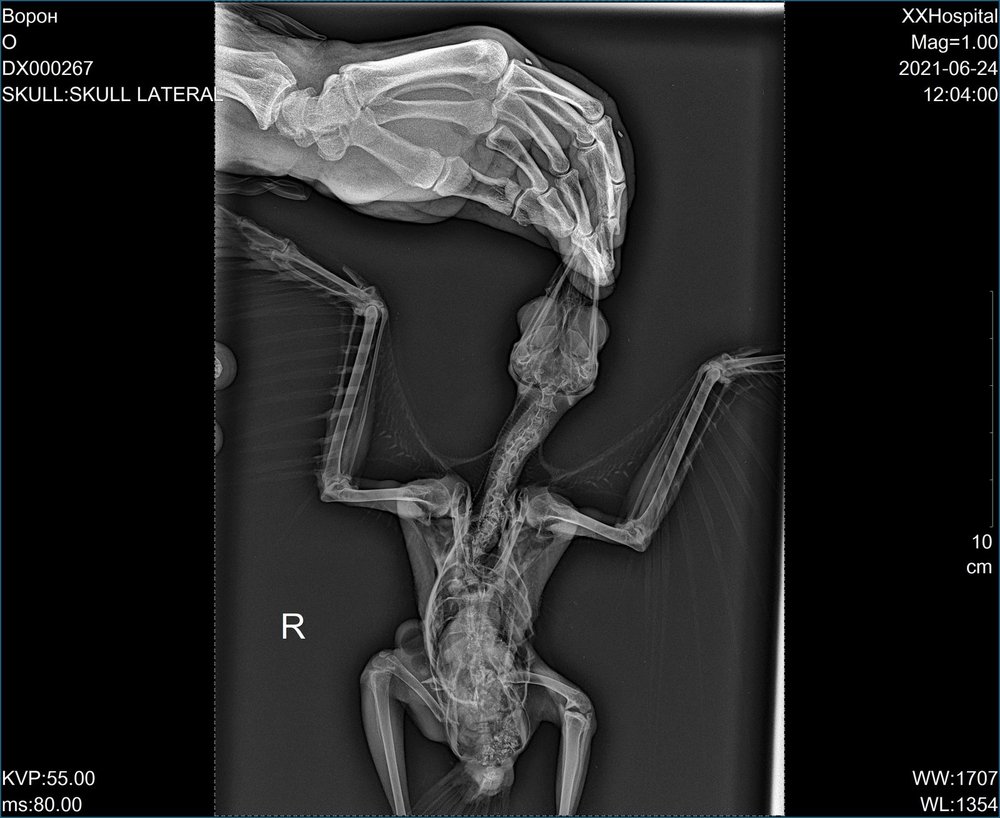

olegru100 Опубликовано 24 июня, 2021 #13 Опубликовано 24 июня, 2021 (изменено) Выкладываем выписку и рентген: На осмотре: - отсутствует чувствительность к боли обоих лап ( мед. иглой). Рентген: - множ. перелом тазобедренной кости, есть осколок (вроде так сказал хирург, он же делал рентген). С позвоночником неясно или не сказали (будут консультироваться с Полиной Юрьевной - до субботы решат). Полина Юрьевна сама не принимает - в декретном отпуске. Назначения в выписке, как я понял, только обезбаливающие. Ждем мнение и назначение медикаментов от врачей форума (пожалуйста направьте спецов в эту тему). Когда вороненок на руках - правую лапу поджимает к телу, левая - висит, но когда ладонью поджимают лапы ( как бы садят на ладонь) левая лапа тоже поджимается как бы правильно, крыльями машет - это все на осмотре. Изменено 24 июня, 2021 пользователем olegru100 измение 1

Набежда Опубликовано 24 июня, 2021 Автор #17 Опубликовано 24 июня, 2021 @With Hooded CrowОчень надеемся, что спасти получиться ребёнка. Только что-то про позвоночник хирург сказал (не поняли мы). Вроде тоже повреждение и лапки обе не работают. До субботы должны заключение сделать в клинике. @With Hooded Crow 1

Набежда Опубликовано 24 июня, 2021 Автор #18 Опубликовано 24 июня, 2021 @With Hooded Crow Да, врачи сказали что бывает, самовосстанавливаются при травме позвоночника. Но вот с ногой, совсем плохо. Но ещё заключительного вывода от врачей нет. Ещё один врач посмотреть снимки должен. @With Hooded Crow

Набежда Опубликовано 24 июня, 2021 Автор #29 Опубликовано 24 июня, 2021 @With Hooded Crow К сожалению у него не только серьёзные травмы, но и не возможность сделать операцию, я не могу объяснить, но как сказали врачи что косточки у него светятся и операцию нет возможности сделать. И еще, они что-то объясняли, но я от волнения забыла. А насчёт динамики, очень ухудшилось его состояние за 10 дней. 1